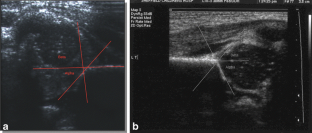

Fig. 2